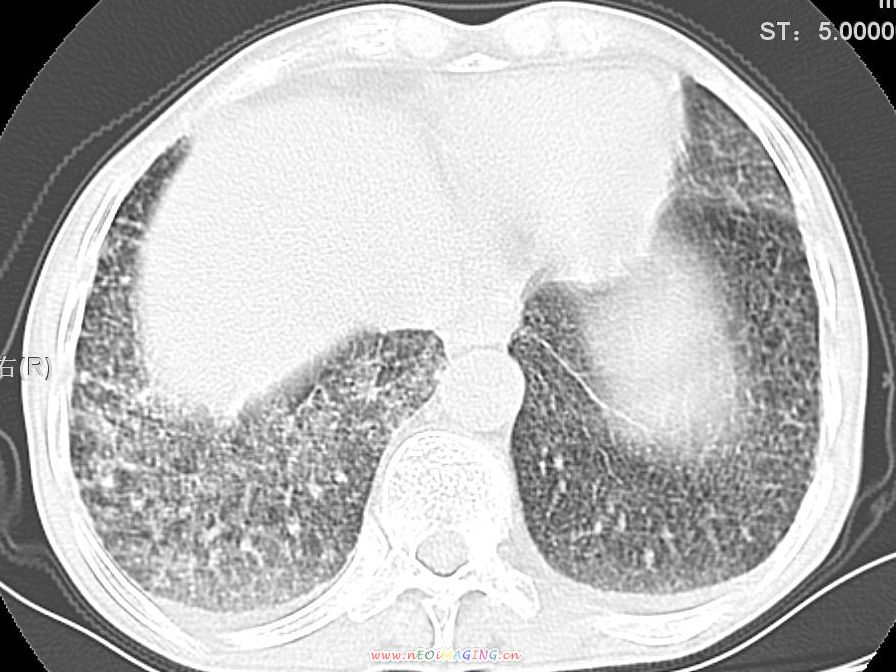

患者咳嗽月余,高热数天,咳黄色稍脓痰。

双肺野分布多个小结节状高密度影,其内散在斑片状模糊影,气管。支气管通畅,纵隔内淋巴结钙化,胸膜局限性增厚粘连,胸腔少量积液。结合病史考虑结核并感染的可能性大,胸膜炎并积液。肺泡癌待排。

纵隔内见钙化的淋巴节,上肺见钙化灶,双肺均匀弥漫分布小结节影,边缘较清楚,能不能考虑是在矽肺的基础上并发的结核和感染,请详细了解病史结合临床.